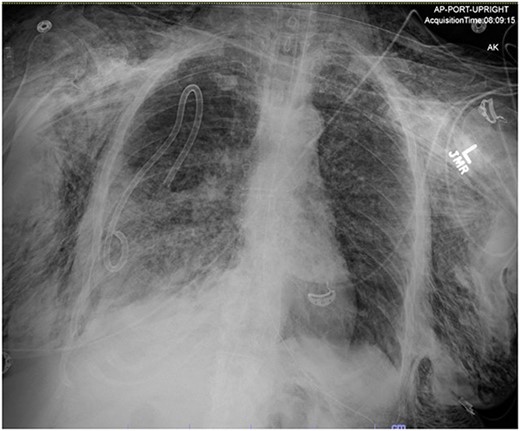

On Hospital Day 2, an interval CXR showed continued resolution of the right-sided pneumothorax but worsening subcutaneous emphysema of the bilateral chest wall and pneumoperitoneum (Fig. 3). Surgical consultation was sought, leading to diagnostic laparoscopy. In the abdomen, emphysematous changes within the gastrohepatic ligament and omental adhesions to the anterior abdominal wall were visualized (Figs 5 and 6). Laparoscopic exploration revealed no diaphragmatic injury or perforated viscera but identified emphysematous changes throughout the preperitoneal space, small and large bowel mesentery, and right paracolic gutter (Figs 7 and 8). Immediate post-op CXR no longer showed evidence of pneumoperitoneum (Fig. 4). The patient was transferred back to the ICU and extubated after three days on Day 5. After the removal of chest tube and transfer to a medical floor on Day 8, the patient developed aspiration pneumonia that was treated with antibiotics. She was discharged on Day 15.

AP upright chest radiograph showing intraabdominal free air, right-sided chest tube in place, and bilateral chest wall subcutaneous emphysema that is worse on the right. Bilateral patchy airspace disease is noted as well.